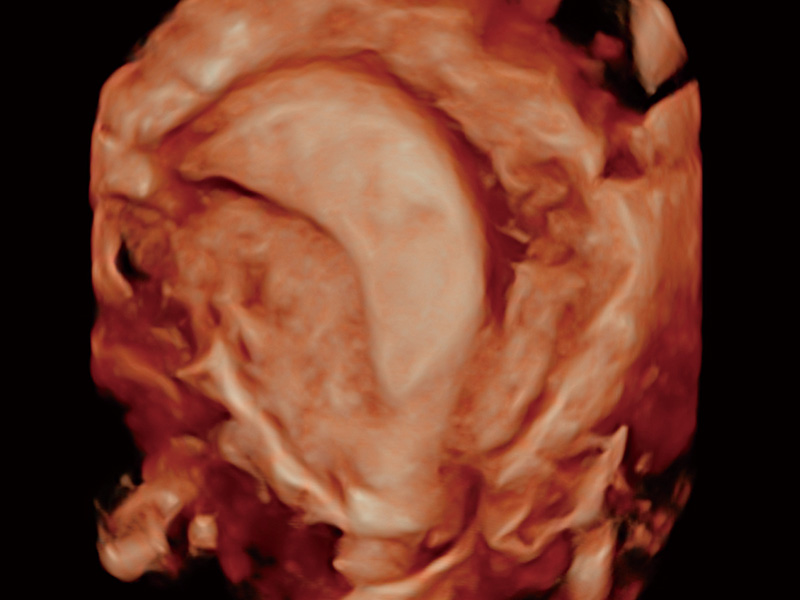

临床图

超声引导下胚胎移植

子宫内膜息肉